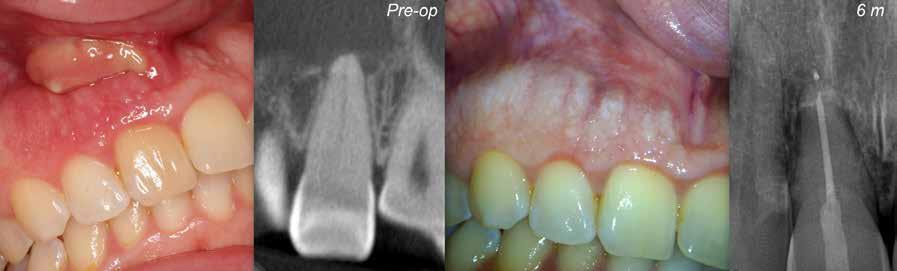

5. a–l. ábrák: Az incisális élen keresztül kialakított hozzáférés lehetővé teszi a pericervikális dentin megőrzését. Kalcifikáció esetén CBCT-felvétel készítése hasznosnak bizonyulhat a hozzáférési nyílás tervezése során (a–d) . Minden fog koronai helyreállítása a gyökértömés elkészítésével egyidejűleg történt. A négyéves (e–h) és a kétéves (i–l) kontrollok alkalmával készített röntgenfelvételeken teljes gyógyulás látható. Mindkét fog tünetmentes és funkcióképes volt. (Dr. Viraj Vora esetei)

Szuvas lézión keresztül történő hozzáférés (a). A fog koronai helyreállítása a gyökértömés elkészítésével egyidejűleg történt (b és c). (Dr. Dale Jung esete)

kialakítása során fennáll a fog labiális irányú perforációjának veszélye, mivel ilyenkor a foganyag elvételét labiális irányú fúrótartással kezdjük. Nemrégiben újragondolták a

hozzáférési nyílás kialakítási protokollt, amelyet már ko

rábban, két endodonciai közleményben közzétettek. Ezekben a frontfogak hozzáférési nyílásainak kialakítását inci

sálisabb megközelítéssel javasolták. 21,22 Az új ajánlásban azt javasolják, hogy a frontfogakban történő hozzáférési nyílás kialakítását a cingulumtól távolabb, inkább az incizális él közelében kezdjük meg 19. Ez lehetővé teszi a lehető legtöbb pericervikális dentin megőrzését és kizárólag a legszükségesebb mennyiségű dentin kerül eltávolításra. Emellett ez a kialakítás a cingulumon keresztül történő hozzáféréshez képest egyenesebb hozzáférést biztosít a labiális és a linguális, vagy palatinális csatornákhoz, valamint lehetővé teszi a csatornák hatékonyabb tisztítását. 21 A fogak kopása esetén a hozzáférést az incisális „felszín” közepén alakítjuk ki (3. a-b ábrák) . A frontfogak kezelése során a megfelelő fúró kiválasztása is kiemelkedően fontos szereppel bír. A korábban ajánlott gömbfúrók használata ma már kifejezetten kontraindikáltnak számít. A gömbfúrók használatakor jellemzően egy fordított tölcsér alakú üreg kerül kialakításra. Ezekben az esetekben az üreg egyre szélesebb lesz, ahogy egyre mélyebbre hatolunk a fúrónkkal (2. a-b ábrák) 23 A gömbfúrók helyett olyan fúrók használata javasolt, amellyel elkerülhető lehet a trepanációs kavitás túlzott mértékű kiterjesztése, és amely segítségével a hozzáférési nyílás legszűkebb részét a pericer -

zésére. Ez azért fontos, mert a frontfogak funkcionális megterhelése során – a PCD-nek megfelelően elhelyezkedő területben – jelentős stressz ébred (5. a–l ábrák) 24 Szükség esetén egy CBCT-felvételt is készíthetünk. A 3D-s adatok jelentős mértékben segíthetik a klinikus munkáját a gyökércsatorna koronális vetületének vizualizálásában, és ennek alapján az egyenes vonalú hozzáférés biztosításához szükséges belépési pont meghatározásában (5.

a–l ábrák) . Ha a kofferdám izolálás a szomszédos fogakra is kiterjesztésre kerül, úgy a kezelést végző orvos sokkal magabiztosabban tudja a gyökerek angulációját vizualizálni (3. a-b ábrák)